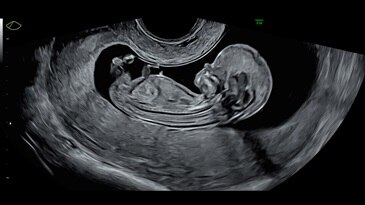

Электронный 4D-датчик eM6C

По сравнению с механическими датчиками конвексный 4D-датчик с электронной матрицей обеспечивает превосходное разрешение и в 16 раз более быстрое получение объемов. Преимущество датчика eM6С заключается в сверхбыстром получении объемов, возможности проведения широкого спектра исследований и исключительной разрешающей способности — как в случае стандартного обследования, так и при проведении расширенного консилиума, например, в случае эхокардиографического исследования у плода.

13-week fetal profile